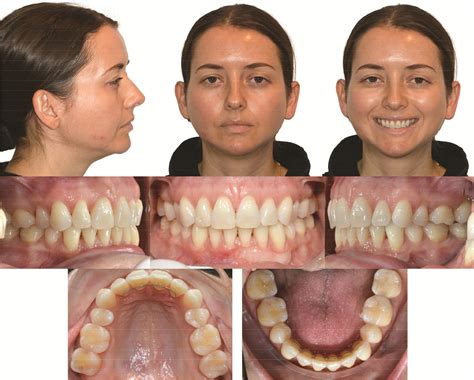

The progression of ICR can lead to significant changes in a person’s bite and facial profile. As the condyle shrinks, the lower jaw (mandible) shifts backward and upward, often resulting in an anterior open bite, where the front teeth no longer meet even when the back teeth are touching. This change can occur rapidly or slowly, often causing distress to patients who notice their smile or facial structure shifting unexpectedly.

Because the condition often mimics other TMJ disorders, diagnosis can be challenging. Patients typically seek help only when they notice visible changes in their appearance or discomfort in their jaw joint. Key symptoms to monitor include:

• Progressive open bite: A noticeable gap developing between top and bottom front teeth.

• Facial asymmetry: A receding chin or a chin that appears to be drifting to one side.